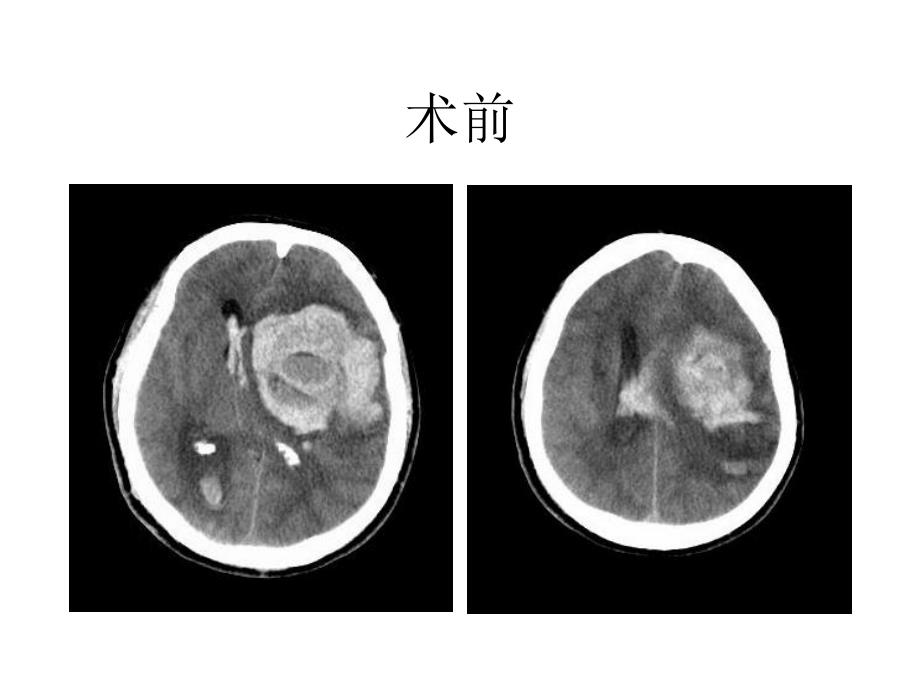

1、脑外科教学查房术前术后 汇报病史 临床体检 辅助检查 病史小结 诊断及依据 鉴别诊断 治疗方案 基底节?基底节区脑出血 基底节|尾状核 豆状核|壳核 苍白球|新纹状体 旧纹状体|病变时出现肌张力降低,运动过多 病变时出现肌张力增高,运动减少 基底节区,影像学名词?包括,基底节及内囊,为一不太明确的区域。内囊,概念很明确,包括内囊前肢、内囊膝部及内囊后肢。基底节,或基底核,指大脑的中心灰质核团,包括尾状核、豆状核、杏仁核和屏状核。广义的基底节是将红核、黑质、及丘脑底核也作为基底神经节的一部分。病理 微动脉瘤 小动脉壁的脂质透明变性病因 原发性脑损害 继发性脑损害 颅内压升高鉴别诊断 出血性脑梗死

2、 动脉瘤破裂 脑动静脉畸形 海绵状血管瘤 烟雾病 颅内肿瘤出血 血液系统疾病内科治疗 一般处理 脑出血急性期高血压的处理 降低颅内压 激素的应用 止血剂的应用脑出血急性期高血压的处理a 脑血流量自动调节机能:人体在不同状态下血压经常变动,但脑血流量则保持不变。脑灌注压:CPP=MAP-ICP脑血流量自动调节对血压的容许变动范围是:MAP=70120mmHg脑出血急性期高血压的处理b 血压的容许的范围内变动时,脑血流量保持不变;MAP低于70mmHg时,脑血流量将明显减少,导致低氧缺血损害,继发急性脑水肿和颅内压升高;若MAP高于120 mmHg,小动脉收缩将被突破而变为被动性扩张,导致过度灌注

3、加重颅高压。而在慢性高血压患者,因其对较高的血压已渐适应,其脑血流的血压调节上限将会上移,甚至高达250mmHg。降低颅内压 甘露醇的药理 使用方法 注意事项 误区外科治疗 级:患者已处于晚期,手术很难奏效。级最适合手术。、级绝大多数适合手术治疗,依病情而定,如血肿量大、内科治疗不佳等。级多发于皮质下或壳核,一般不需手术,但血肿量30ml可考虑手术。手术方法 开颅血肿清除术 钻孔微创颅内血肿清除术 手术录像 脑卒中的外科治疗.rmvb影响手术效果的因素 患者年纪 意识水平:出血量及部位:手术时机:手术方式:常见并发症的预防和治疗 消化道出血 肺部感染 急性肺水肿恢复期治疗 急性期康复治疗 恢复期的治疗1.功能锻炼2.药物治疗3.高压氧治疗4.语言训练5.心理康复谢谢